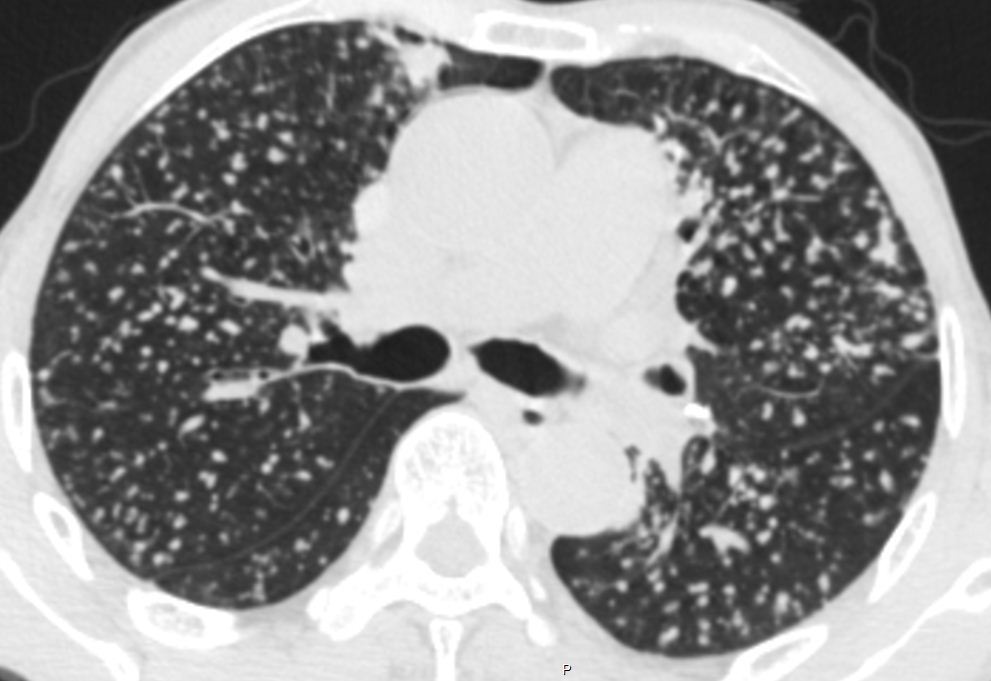

尘肺CT

尘肺,这个最经典!